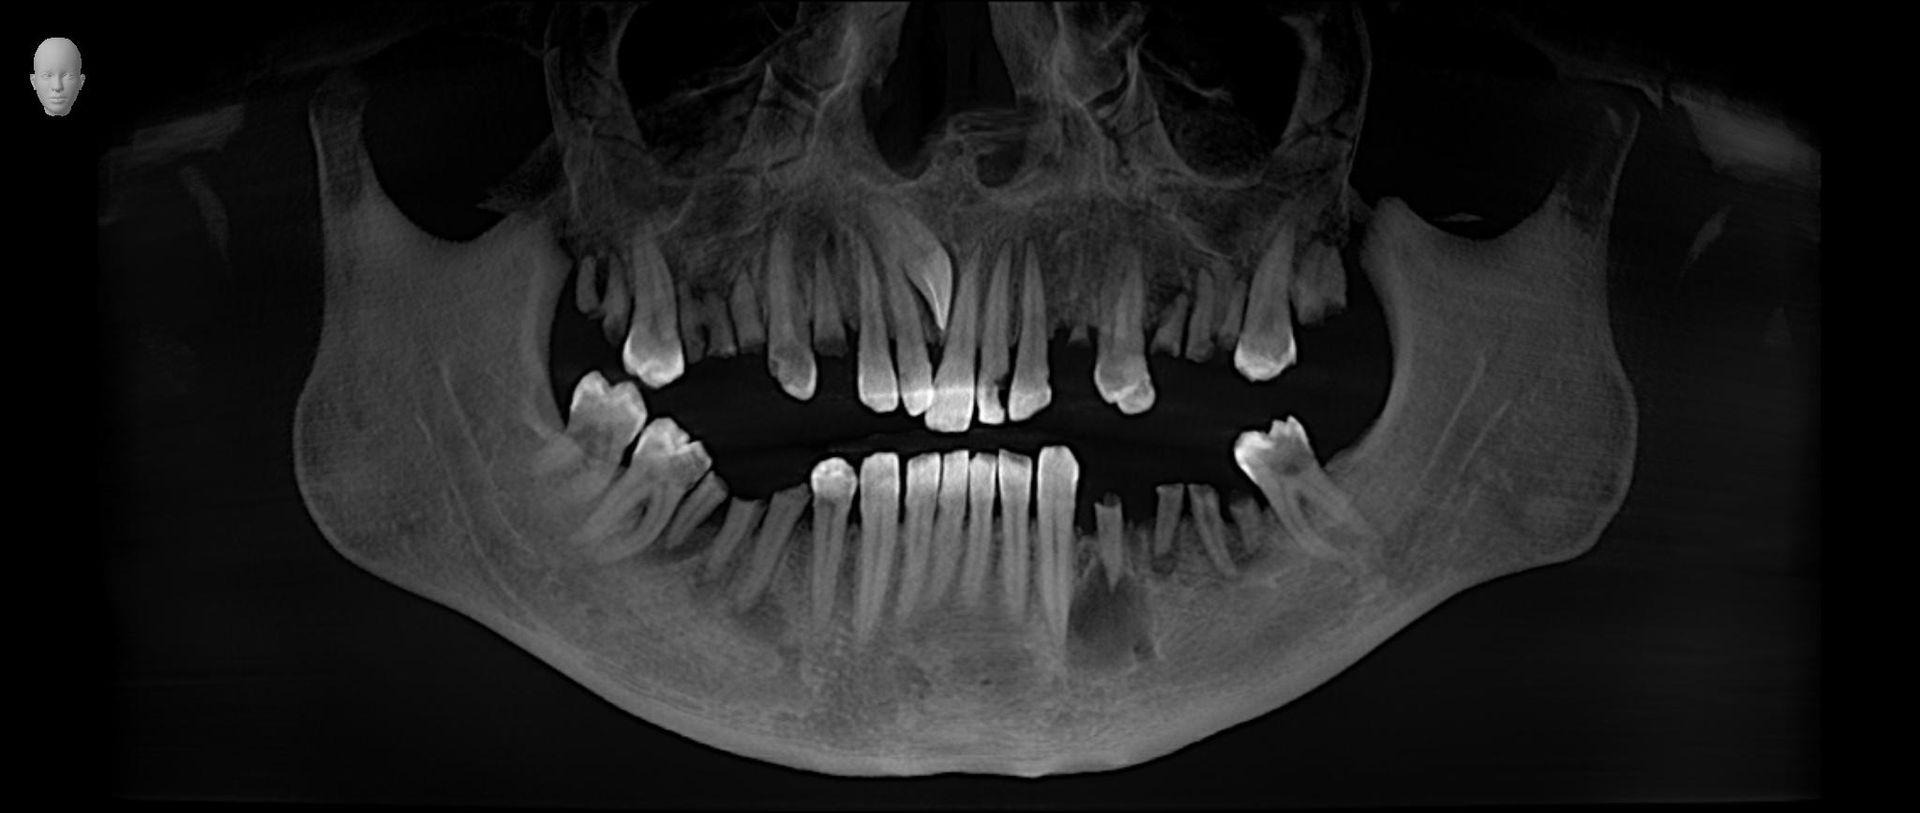

Esame diagnostico che permette di valutare, con precisione, la densità ossea mascellare e mandibolare, richiesto dai dentisti, in quanto indispensabile prima di un intervento di implantologia.

Trova indicazione anche in ortodonzia per lo studio dei denti inclusi, soprannumerari ed ectopici e in endodonzia.